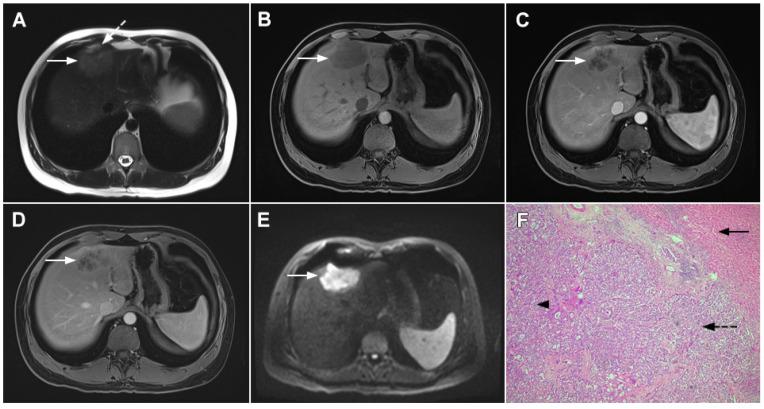

Intrahepatic cholangiocarcinoma (ICC) is the second most common primary hepatic malignancy, with mass-forming growth pattern being the most common. The typical imaging appearance of mass-forming ICC (mICC) consists of irregular ring enhancement in the arterial phase followed by the progressive central enhancement on portal venous and delayed phases. However, atypical imaging presentation in the form of hypervascular mICC might also be seen, which can be attributed to distinct pathological characteristics. Ancillary imaging features such as lobular shape, capsular retraction, segmental biliary dilatation, and vascular encasement favor the diagnosis of mICC. Nevertheless, these radiological findings may also be present in certain benign conditions such as focal confluent fibrosis, sclerosing hemangioma, organizing hepatic abscess, or the pseudosolid form of hydatid disease. In addition, a few malignant lesions including primary liver lymphoma, hemangioendothelioma, solitary hypovascular liver metastases, and atypical forms of hepatocellular carcinoma (HCC), such as scirrhous HCC, infiltrative HCC, and poorly differentiated HCC, may also pose a diagnostic dilemma by simulating mICC in imaging studies. Diffusion-weighted imaging and the use of hepatobiliary contrast agents might be helpful for differential diagnosis in certain cases. The aim of this manuscript is to provide a comprehensive overview of mICC imaging features and to describe useful tips for differential diagnosis with its potential mimickers.

肝内胆管细胞癌(ICC)是第二常见的原发性肝恶性肿瘤,以肿块型生长方式最为常见。肿块型肝内胆管细胞癌(mICC)的典型影像学表现为动脉期不规则环状强化,随后门静脉期和延迟期进行性中央强化。然而,也可能出现富血供型 mICC 的不典型表现,这可归因于其独特的病理特征。辅助影像学特征,如小叶形状、包膜回缩、节段性胆管扩张和血管包绕,有助于 mICC 的诊断。然而,这些影像学表现也可能存在于某些良性病变中,如局灶性融合性纤维增生、硬化性血管瘤、化脓性肝脓肿或包虫病的假实质性形式。此外,少数恶性病变,包括原发性肝淋巴瘤、血管内皮细胞瘤、孤立性低血供肝转移瘤和不典型的肝细胞癌(HCC)形式,如硬癌型 HCC、浸润性 HCC 和低分化 HCC,也可能在影像学研究中模拟 mICC,导致诊断困难。弥散加权成像和肝胆对比剂的使用可能有助于某些情况下的鉴别诊断。本文旨在全面概述 mICC 的影像学特征,并描述与潜在类似物进行鉴别诊断的有用技巧。